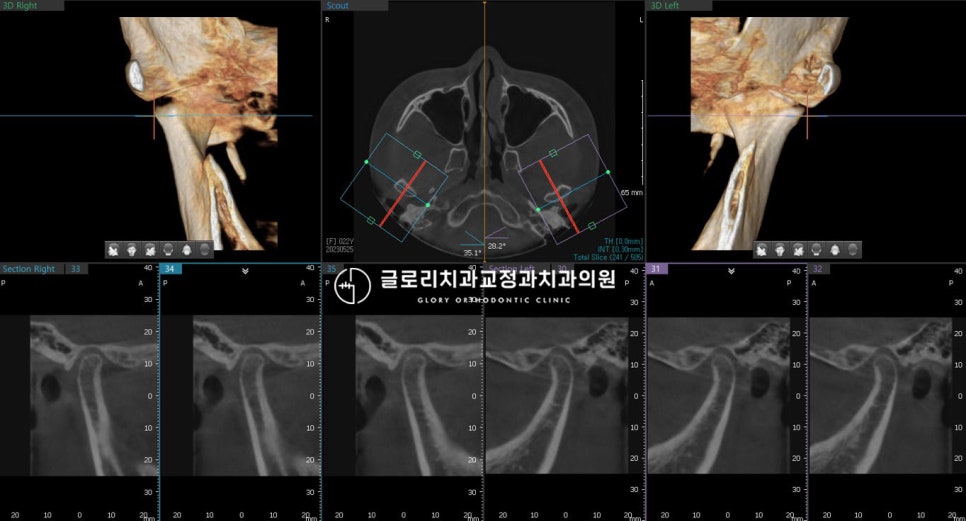

『2. 시작 전 턱관절(TMJ) 체크』

치료를 시작하기 전

턱관절에는 문제가 없는지도

꼼꼼하게 살펴보았습니다.

간혹 앞니 치아교정을 시작한 뒤

턱관절의 통증을 호소하시는 경우가 있어

망우역 치과 의 엑스레이와 CT를 촬영해

꼼꼼하게 확인한 뒤 진행을 하는데요.

이 환자의 경우

진료 전 TMJ와 과두에는 문제가 없으나,

중간에 재위치되어 움직일 경우

치료 계획이 변경 가능성이 존재합니다.

그렇기 때문에 월마다 오셔서

치열과 더불어 TMJ에도 불편한 점은 없는지

면밀히 체크해 드리기로 했습니다.